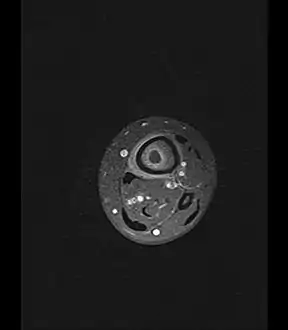

Axial T1-weighted MRI pre-contrast enhancement showing that the intramedullary collection is T1-hyperintense suggesting proteinaceous viscous fluid consistent with infection.

Axial T1-weighted fat-saturated MRI image following IV gadolinium contrast demonstrating the intramedullary lytic area seen on radiography to be ring enhancing consistent with a purulent fluid collection. Extensive circumferential periosteal enhancement is noted. There is also substantial bone marrow enhancement.